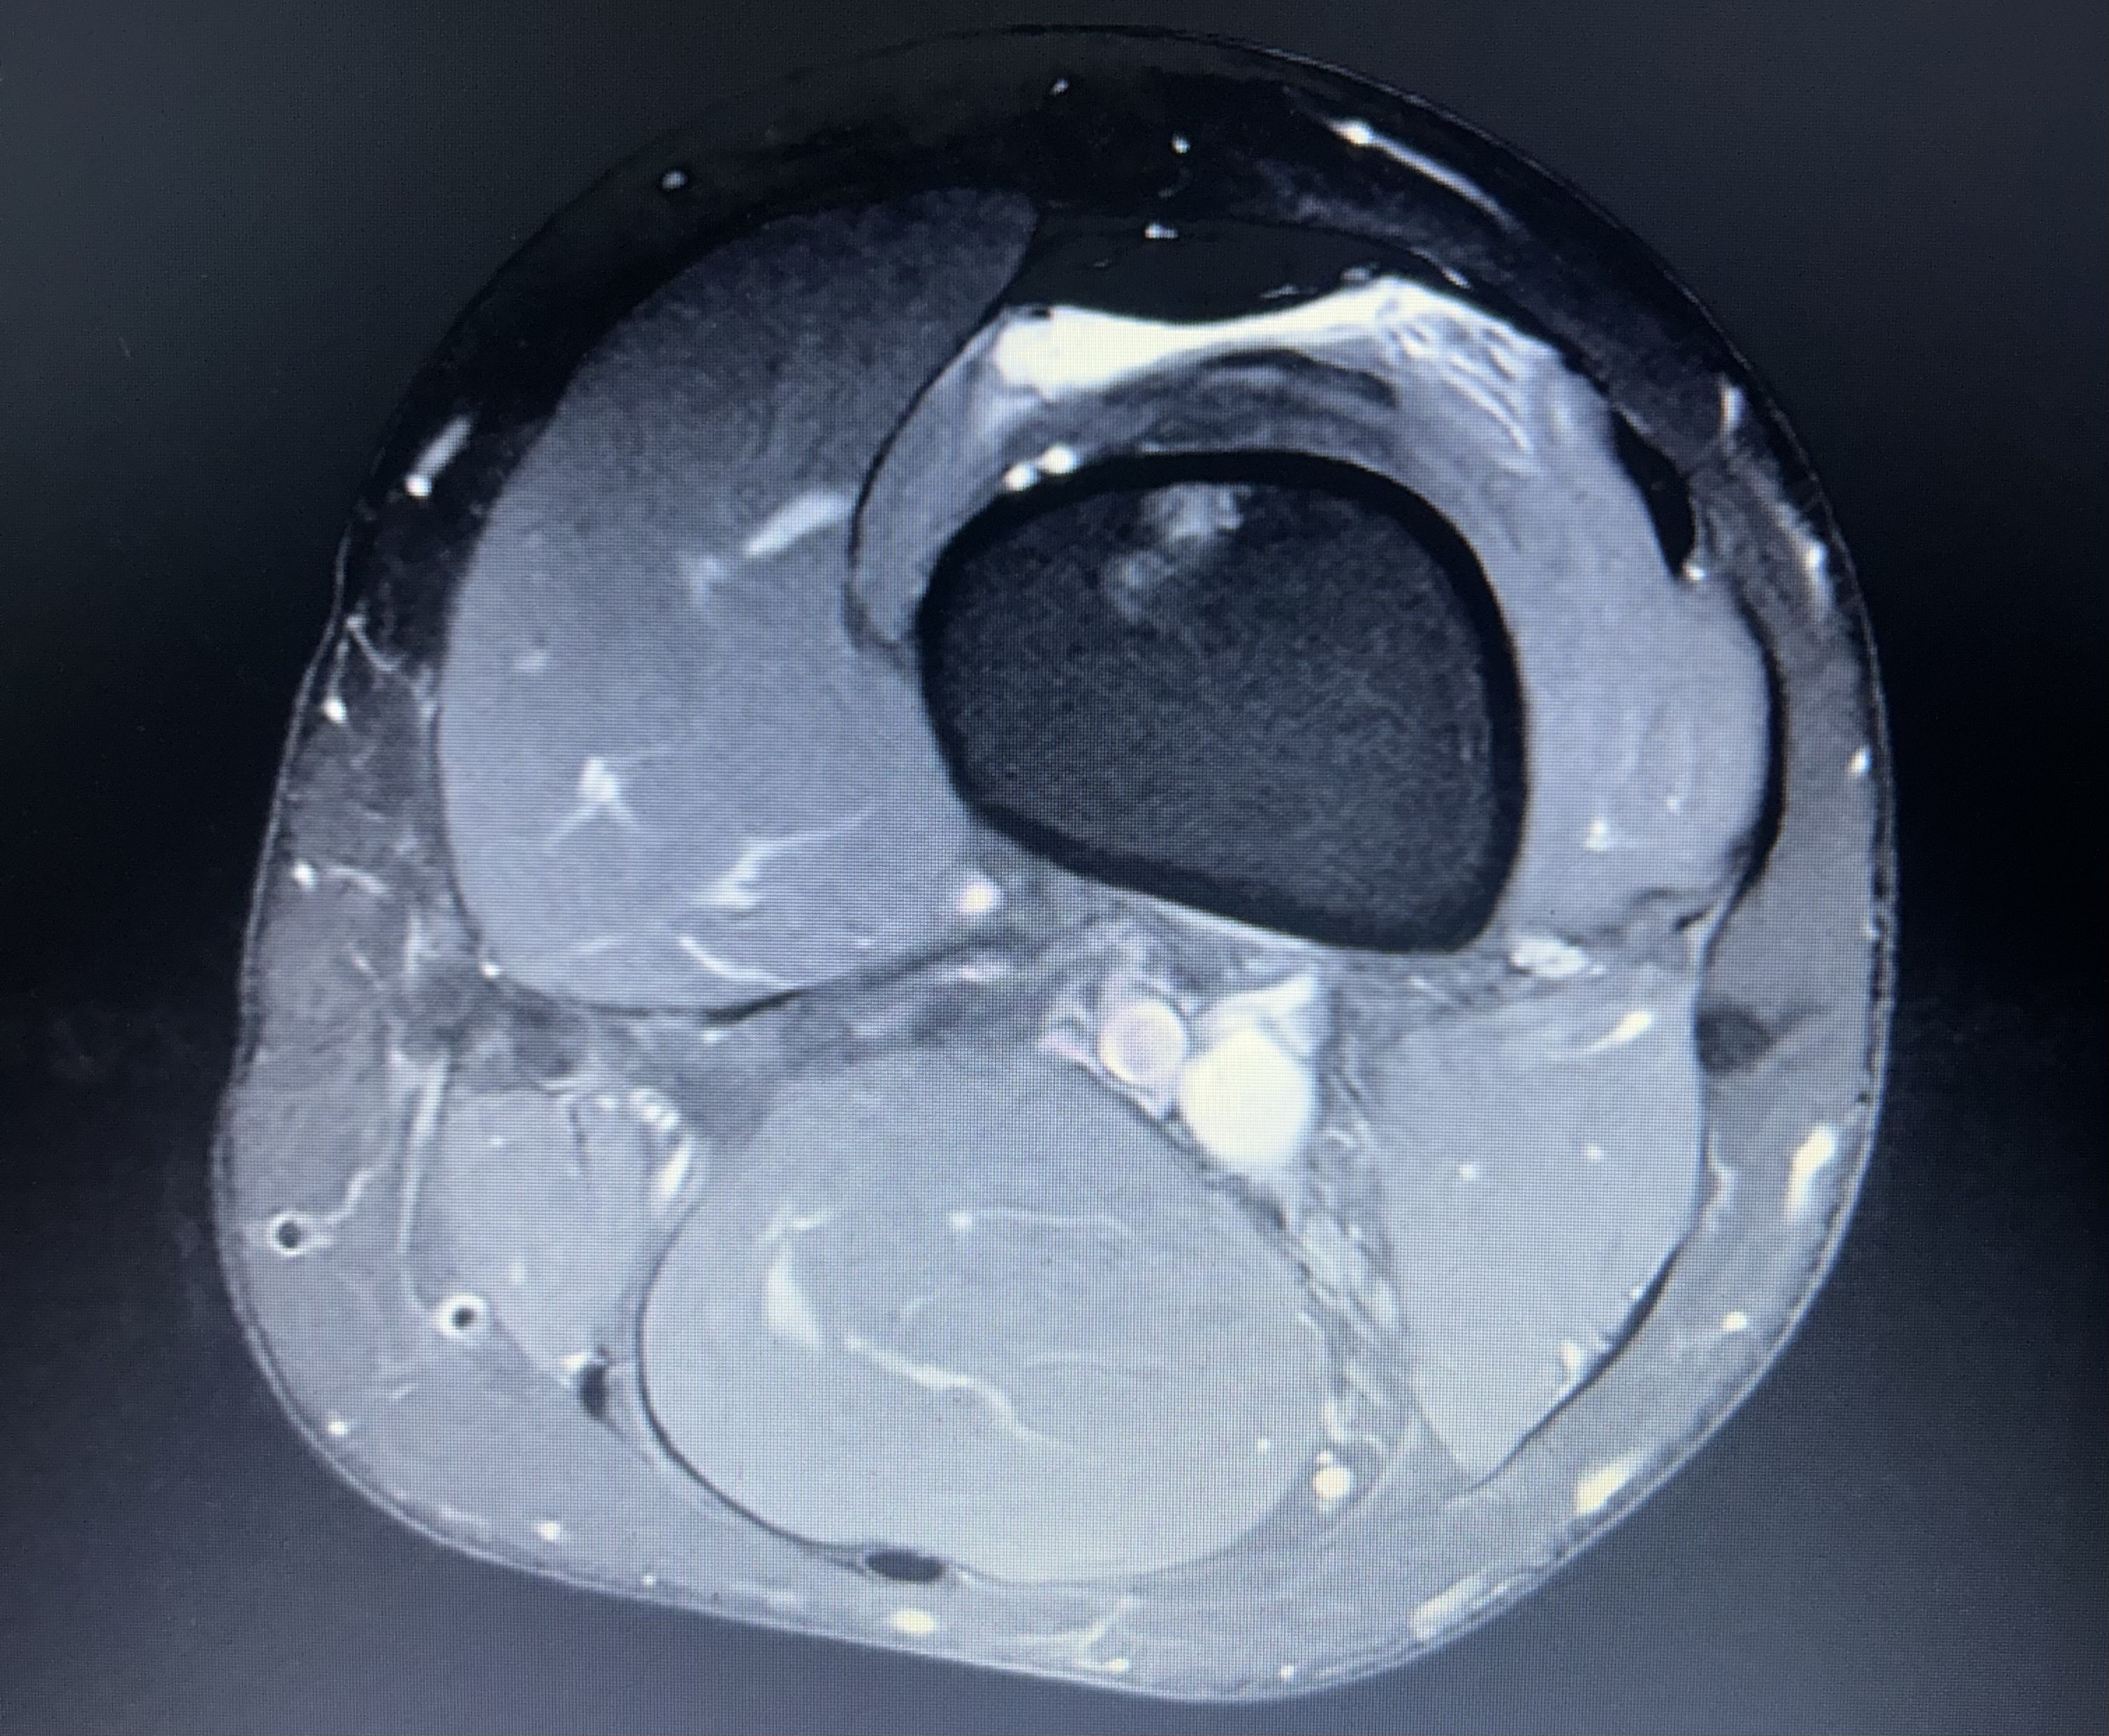

In the world of Site Reliability Engineering (SRE), if your logs are ambiguous, you look for better telemetry. In orthopedics, that telemetry is the MRI.

Before my first surgery, the clinical consensus was “wait and see.” The doctors were unclear on the extent of the damage, stating they wouldn’t know for sure until they were “inside the knee” on surgery day. As a former collegiate athlete and an engineer, “wait and see” wasn’t a satisfying roadmap.

I decided to upload my raw MRI images to Gemini. Leveraging its advanced multimodal reasoning, Gemini identified a meniscus root tear—a specific, high-stakes injury that requires a much different surgical approach than a standard trim.

The Result: When the surgeon finally performed the procedure, Gemini’s “prediction” was confirmed. Having this insight early allowed me to mentally and logistically prepare for a non-weight-bearing recovery, rather than being blindsided post-op. This was my “Aha!” moment: Gemini is now my primary LLM because it doesn’t just process text; it “sees” complex data with architectural precision.